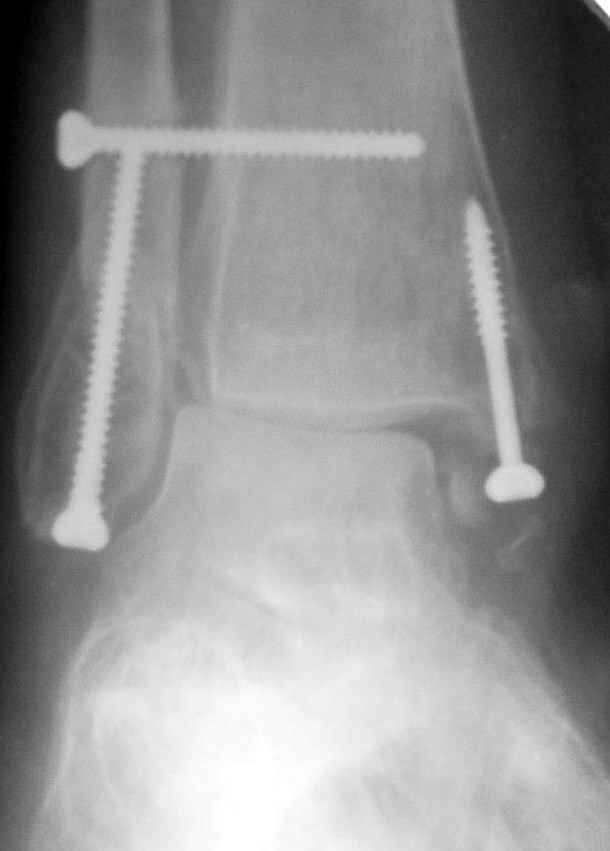

До операции 28 июля

Операция 29 июля